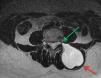

Imágenes de RM, planos axiales. A. Imagen potenciada en T1, con saturación de la grasa; el quiste hidatídico (flecha roja) está situado en el espesor de la musculatura paravertebral lumbar izquierda, es hipointenso y su contenido es homogéneo. Nótese la íntima relación del aspecto más anterior y medial de la lesión con el agujero de conjunción izquierdo de L4-L5 (flecha verde). B. Imagen potenciada en T1, con saturación grasa y obtenida tras la administración de contraste intravenoso, en la que no se observan captaciones de contraste a nivel de la lesión quística (flecha roja).

Imagen de RM potenciada en T2 y sin saturación de la grasa, plano axial. El quiste hidatídico (flecha roja) se muestra hiperintenso, de contenido homogéneo. Nótese nuevamente, pero con mayor claridad, el íntimo contacto de la vertiente más anterior y medial de la lesión con el agujero de conjunción izquierdo de L3-L4 (flecha verde), y el aspecto unilocular de la lesión por la ausencia de vesículas hijas que dan el patrón multivesicular o multiseptado característico del quiste hidatídico más evolucionado que el de nuestro caso. Estas características predispusieron al diagnóstico radiológico inicial erróneo de quiste extradural meníngeo.